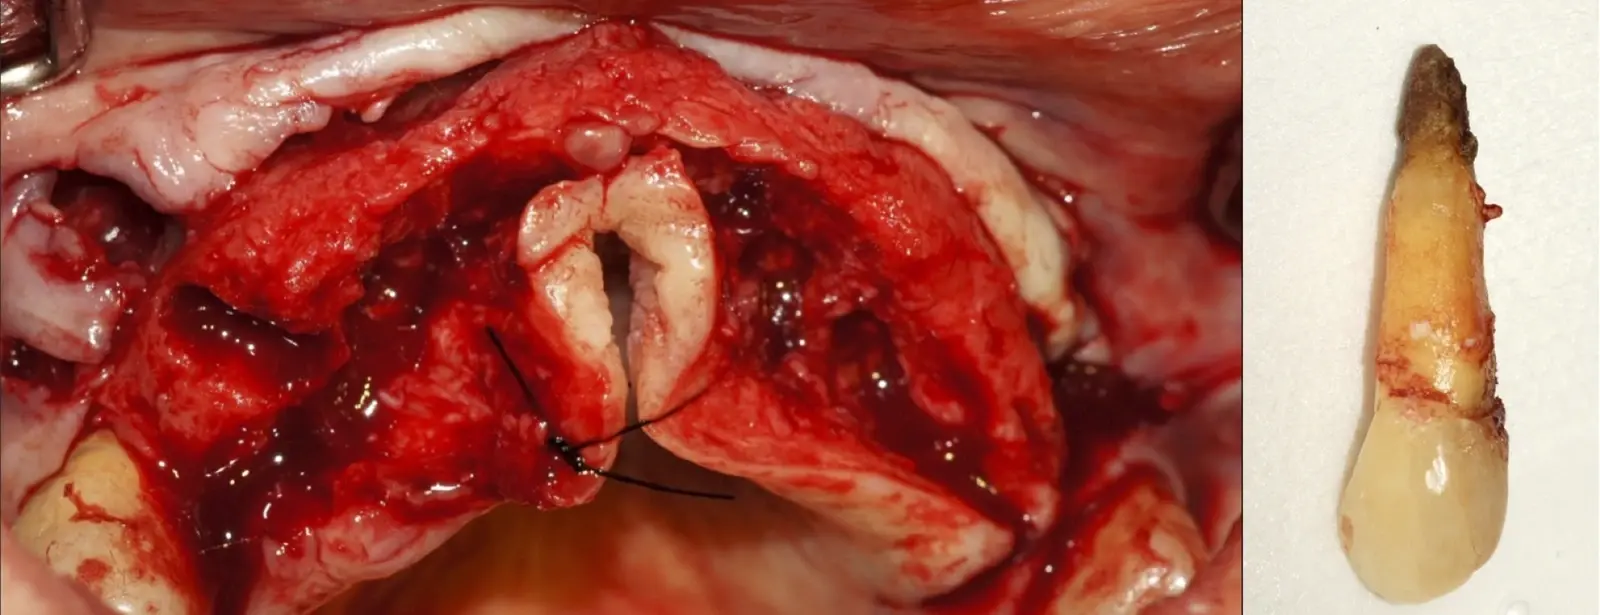

El procedimiento se inicia colocando anestesia y elevando un colgajo mucoperióstico a espesor completo y exponiendo la zona. En seguida se realiza la enucleación de la lesión, eliminando o creando una ventana en la lámina cortical que contiene el área del ápice.

El procedimiento se inicia colocando anestesia y elevando un colgajo mucoperióstico a espesor completo3 (incisión semilunar o intrasurcular con/sin protección papilar) y exponiendo la zona. En seguida se realiza la enucleación de la lesión, eliminando16 o creando una ventana17 en la lámina cortical que contiene el área del ápice; este retiro óseo se realiza con los insertos de forma aplanada dentada o inserto con cobertura diamantada plano o redondo, recordando ser lo más conservador posible (Figura 5).

Después de realizado el acceso e identificado el ápice, se procede a la limpieza de la zona con instrumentos manuales y/o con insertos diamantados de parte activa angulada para poder eliminar todo el tejido patológico del perímetro radicular apical y del tejido óseo circundante (Figura 6).

Una vez limpia la zona apical, se corrobora la integridad de la raíz y se evalúa el grado de extensión de la lesión. Si el defecto óseo es pequeño, se procede a realizar la preparación del conducto y obturación retrógrada de ser el caso. Si el defecto óseo es de gran tamaño e inaccesible a los insertos, se procede a realizar un corte de por lo menos 3 mm de ápice radicular conteniendo los posibles conductos aún infectados11 empleando habitualmente insertos de borde aserrado con/sin marcas de medición para un trabajo seguro7 (Figura 7).

Para la obturación retrograda, el sellador más usado es el agregado de trióxido mineral (MTA)21 por sus propiedades hidrofílicas y de biocompatibilidad que favorece la neoformación ósea.3 Luego de la desinfección y secado, se realiza la obturación-compactación de rutina y se culmina con la reposición de los tejidos gingivales a través de puntos de sutura (Figura 10).